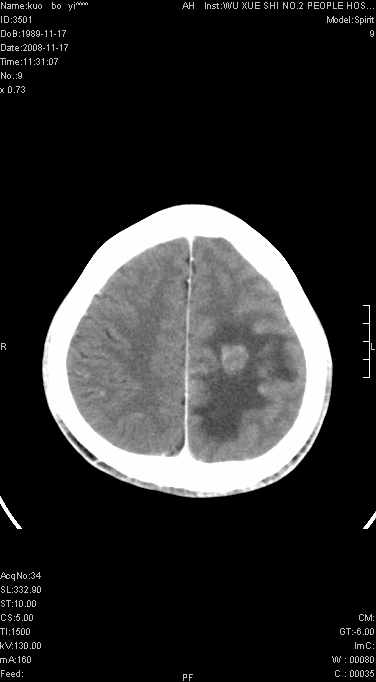

右侧肢体无力一周

这么大片面积,中线居中,占位效应不明显,考虑脑梗塞。

灶中央有厚环状高密度成分,顶叶皮质局部有显著的受压表现,多支持占位性病变,胶质瘤?淋巴瘤?转移?不知患者年龄多大,病史较短,不除外炎性

增强后水肿中心高密度灶有明显强化,强化不均匀,呈雪花状或絮状,且强化明显,若为肿瘤,应该出现形态较规则的瘤体影,强也有例外如胶质瘤就可以形态不规则.但胶质瘤明显强化者多为恶性间变性,与病史及相关表现太不相符.因此本例多考虑为炎症引起.

左顶叶较大范围水肿区,内见明显强化的片状 棉絮状组织,但占位效应不明显。多考虑:脑炎!

还是考虑原发脑胶质瘤,梗塞缺血水肿的低密度要同时累及皮、髓质并要符合动脉供血的区域分界特点,本例强化后见瘤体结节及向周围浸润生长的瘤血管都强化了,水肿广泛呈指状,占位效应使同侧脑皮质受压变薄、脑沟消失但因实质性的瘤体尚小所以中线无明显移位。不知各位同意这样分析吗?(转移瘤多为多处病灶)

首先考虑脑胶质瘤。有明显的左顶叶脑白质水肿,病变轻度占位效应,花环样强化,脑炎——影像不支持!

不像脑梗死,低密度区中心,有一密度增高边界清楚的,近脑组织密度的病灶.建议进一步强化及肺和肝等重要脏器检查.